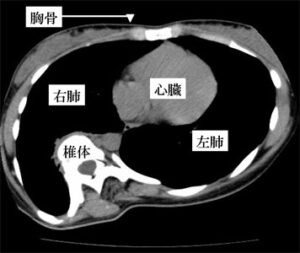

※本来、椎体は胸部の方向に向いていますが、椎体の回旋のために、全く別の方向に向いています。さらに、回旋した椎体は右の胸部を変形させて右肺を圧迫しています。

すなわち、正面から見ると脊柱が左右に曲がっている状態(側弯)、側面から見ると正常範囲からの逸脱(胸椎部の過剰な後弯、前弯、胸腰椎部の後弯など)、そして、これらの変形に伴う椎体のねじれ(回旋)が脊柱側弯症の病態です。(図2)